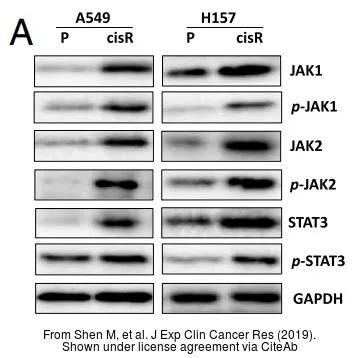

TargetJAK1

- Target descriptionJanus kinase 1